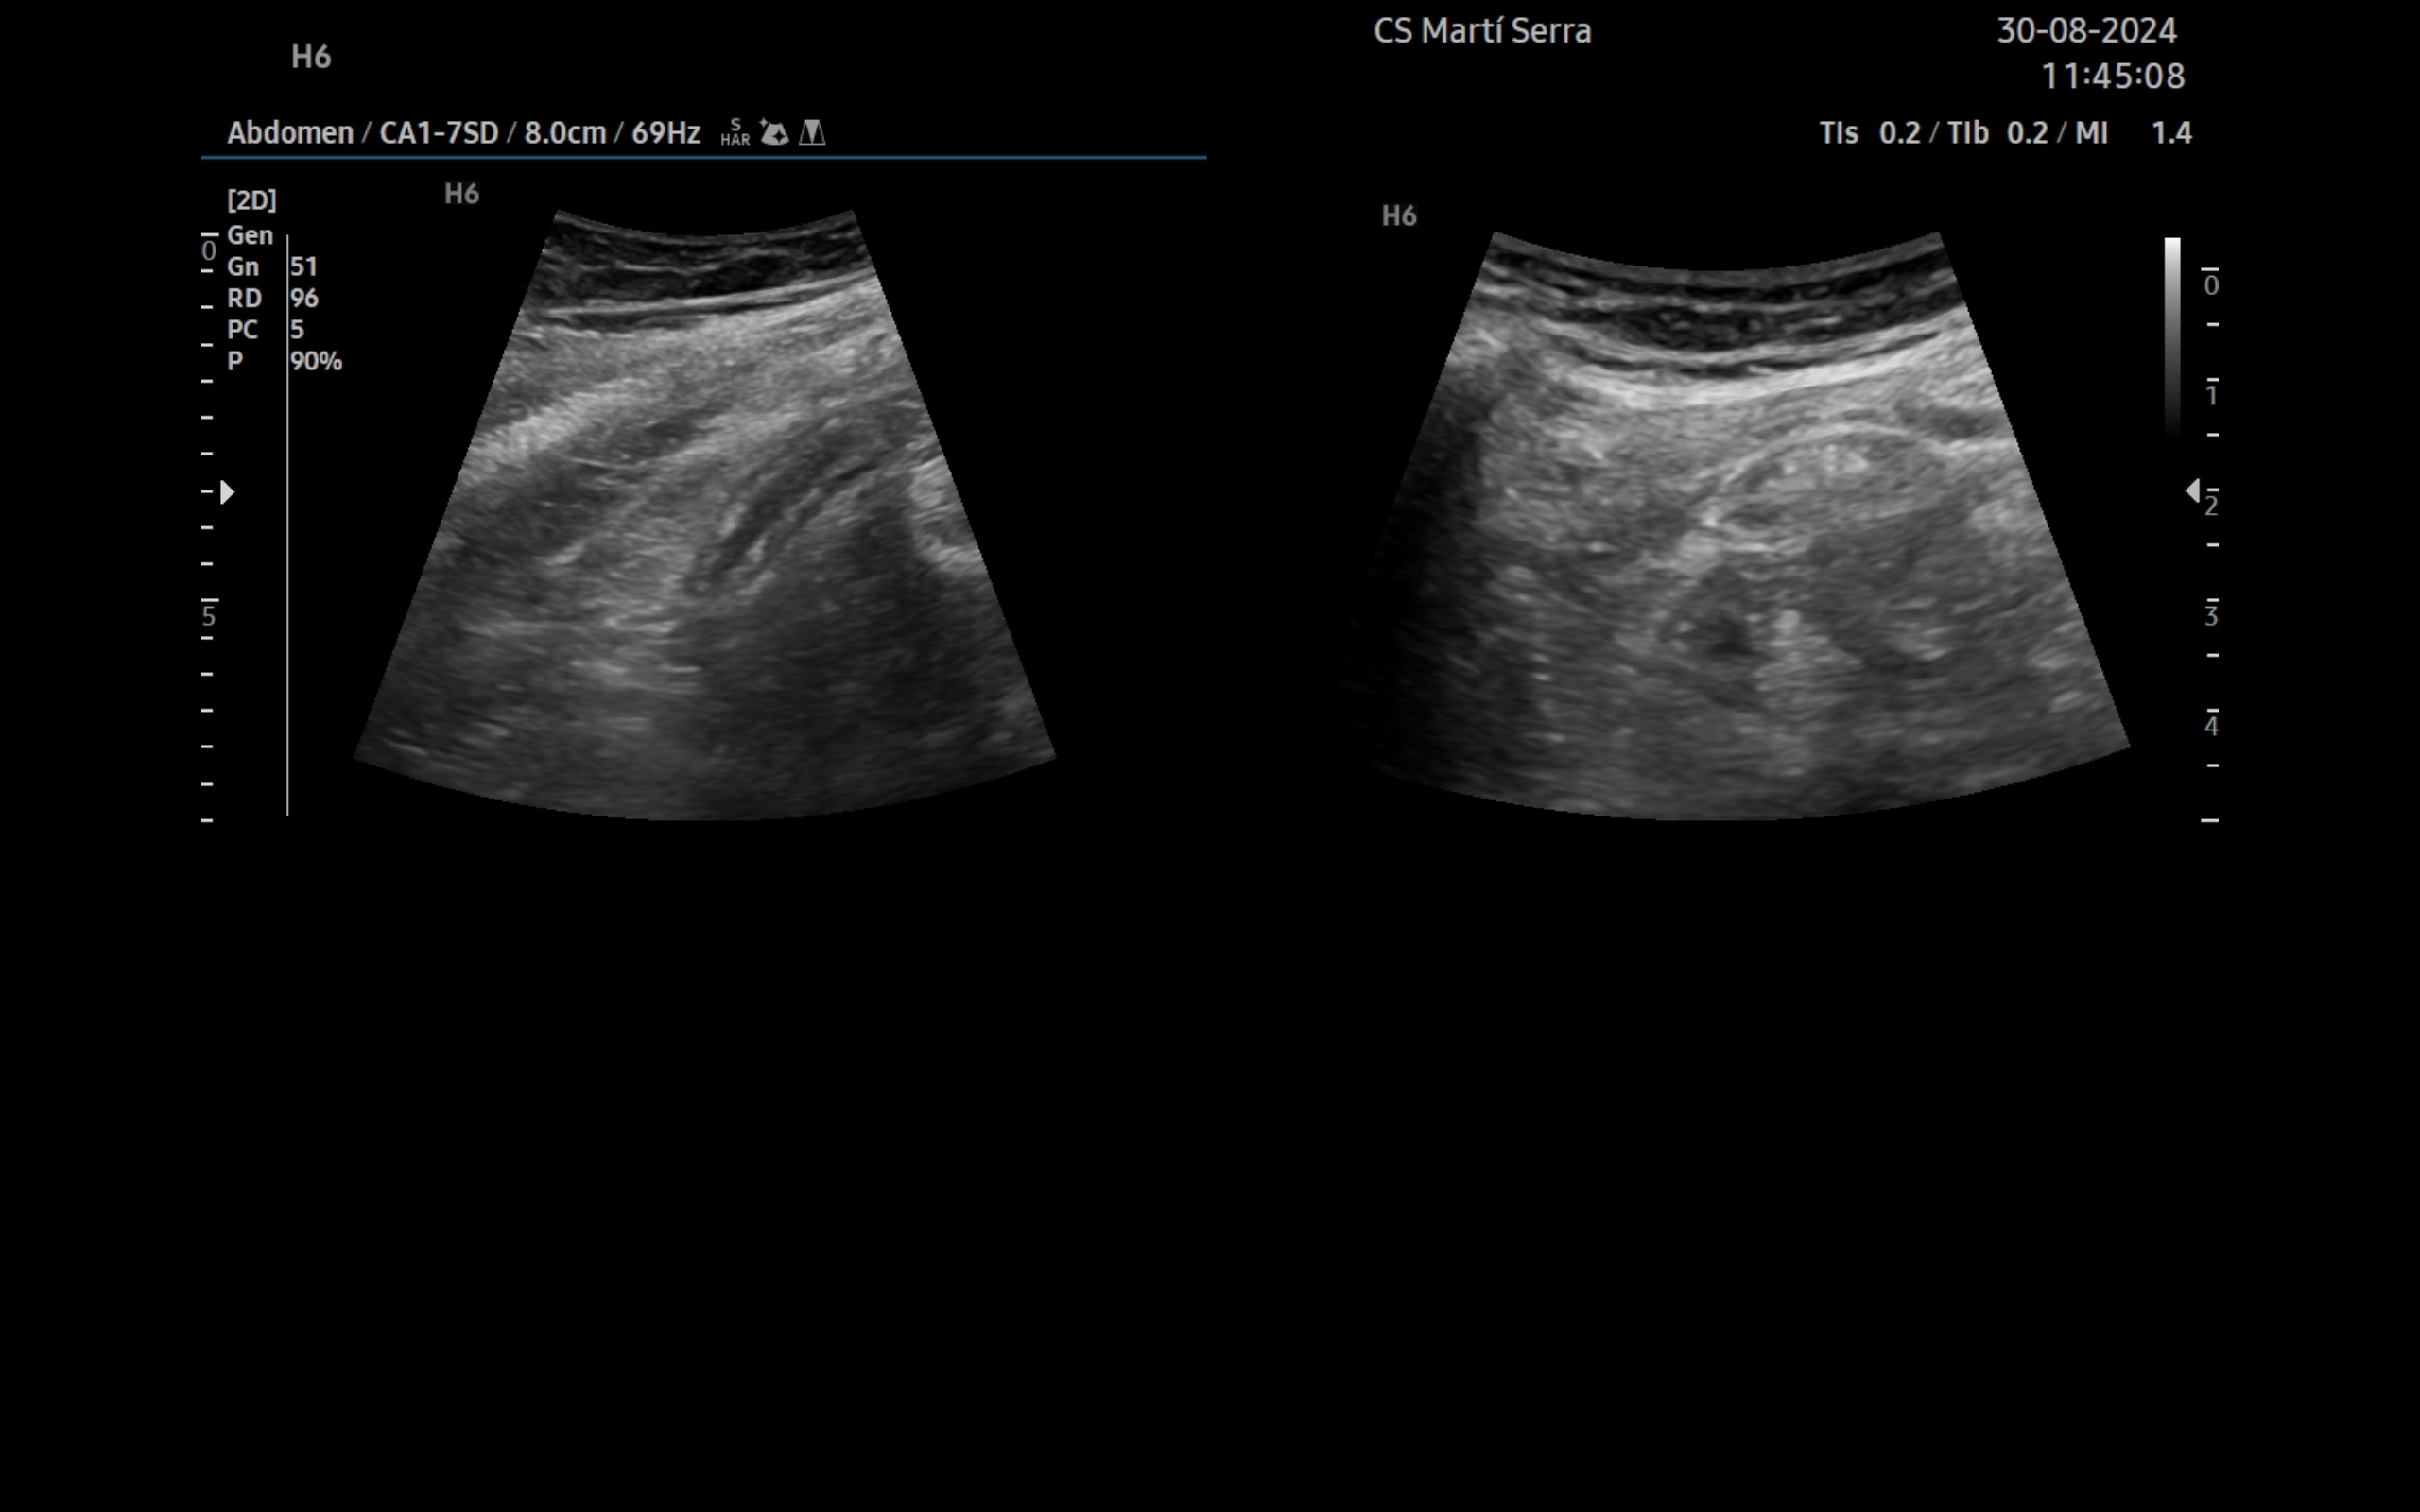

Ecografía clínica:

Imagen hiperecogénica con sombra en interior de vesícula biliar, hígado, páncreas, bazo y riñones sin alteraciones, vejiga orina poco replecionada. Llama la atención mínima imagen anecogénica en fondo de saco de Douglas. Apéndice visible en fid con diámetro 1,07 cm con captación aumentada con apendicolito con fenómeno centelleo.

Buena evolución posterior.La ecografía complementa la anamnesis y la exploración física. A día de hoy está disponible en la mayoría de centros de salud. En el caso concreto de la paciente, la discapacidad intelectual limitó la información obtenida de la entrevista. Ante la detección de un apéndice con diámetro mayor de 6 mm, no compresible, captación aumentada y apendicolito, se ha podido diagnosticar el proceso.